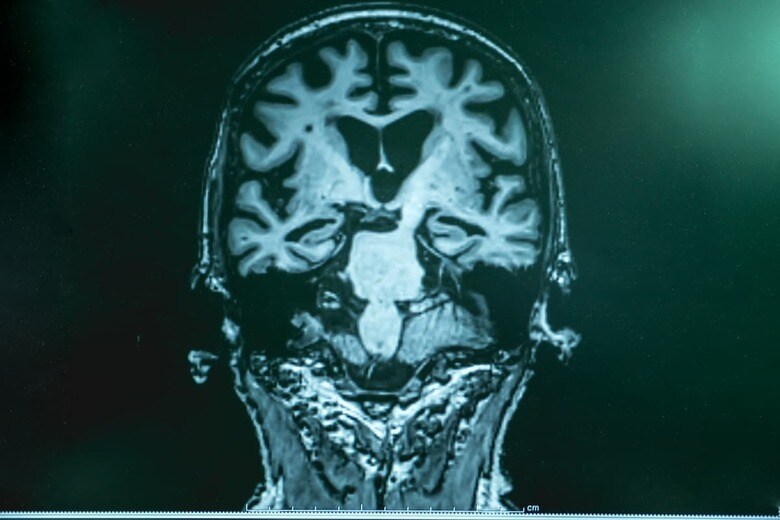

日本におけるアルツハイマー型認知症は認知症患者の半数を占め、今後も増加の一途をたどることは必至だ。糖尿病専門医の牧田善二さんは「アルツハイマー病の発症メカニズムは、糖尿病とそっくりで、予備軍が多い。また現状、アルツハイマー病を発症してから治す方法はなく予防が重要ですが、発症前の段階での治療は今日の日本の医療保険制度ではできません」という――。

世界一、アルツハイマー病に罹りやすい日本人

日本人は世界一、アルツハイマー病(アルツハイマー型認知症)に罹りやすい国民と言えます。

※アルツハイマー型認知症は認知症の半分以上を占める。

理由の1つは、日本人の寿命が長いことにあります。アミロイドβは、アルツハイマー病の症状が現れる20年くらい前から少しずつ脳に蓄積していることがわかっています。